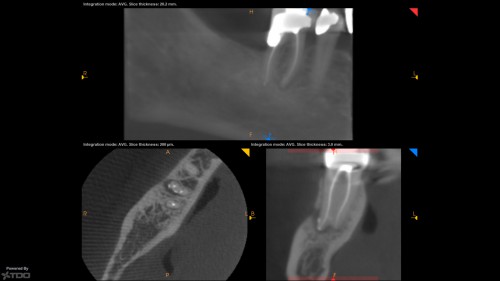

By michael trudeau / August 16, 2018

http://theendofix.com/category/dailyfix/ Cheers, Mike